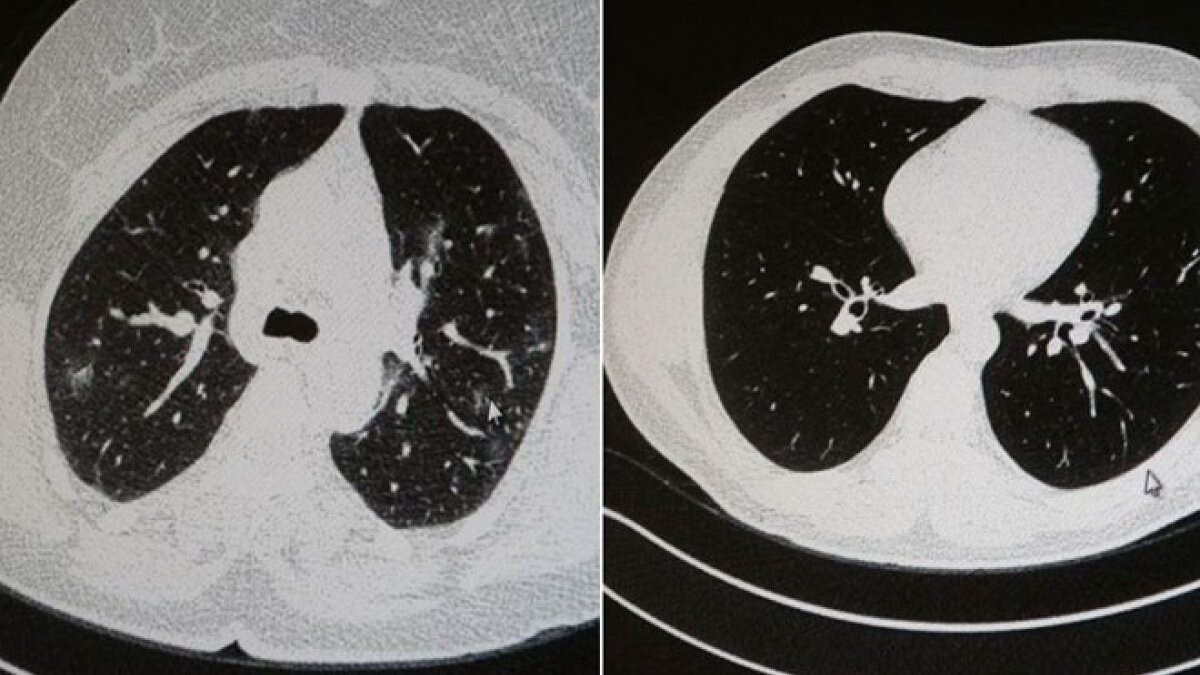

Elazığ'da Göğüs Hastalıkları Uzmanı Dr. Cebrail Azar, genç olduğu halde aşı olmayanlarda hastalığın ağır seyrettiğini ifade ederek "Ben gencim, benim bağışıklık sistemim kuvvetli" diyen genç bir hastanın akciğerlerinde ciddi lekelenmelerin olduğunu ve buna koronavirüs zatürresinin yol açtığını dile getirdi.

Azar, aynı şekilde aşı olup koronavirüs hastalığına yakalanan bir başka genç hastanın akciğer tomografisinde herhangi bir sorunun olmadığını ve hastanın durumunun iyi olduğunu gözlemlediklerini kaydetti.